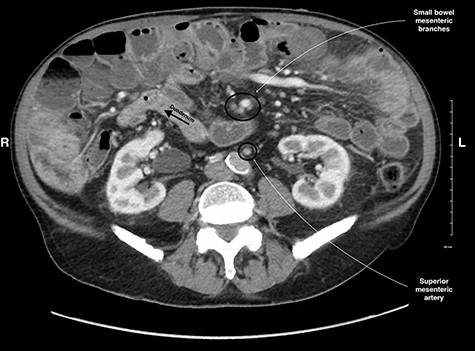

A 79-year-old male presented with 2 weeks of persistent abdominal pain. He did not report any nausea, vomiting or chills. Past medical history included aortic stenosis and type II diabetes, and no history of previous abdominal surgery. His abdomen was soft, non-distended, with mild generalized tenderness and an incidental umbilical hernia. Vitals signs were normal. His white blood cell count was 16.7 × 109/L. CT identified multiple distended and inflamed jejunoileal diverticula. There was no free fluid or gas (Fig. 1). The patient was admitted with small bowel diverticulitis and managed with bowel rest and intravenous antibiotics. He was discharged on post-admission Day 3.

CT scan of the abdomen and pelvis showing small bowel diverticula with inflammation and stranding consistent with uncomplicated diverticulitis.